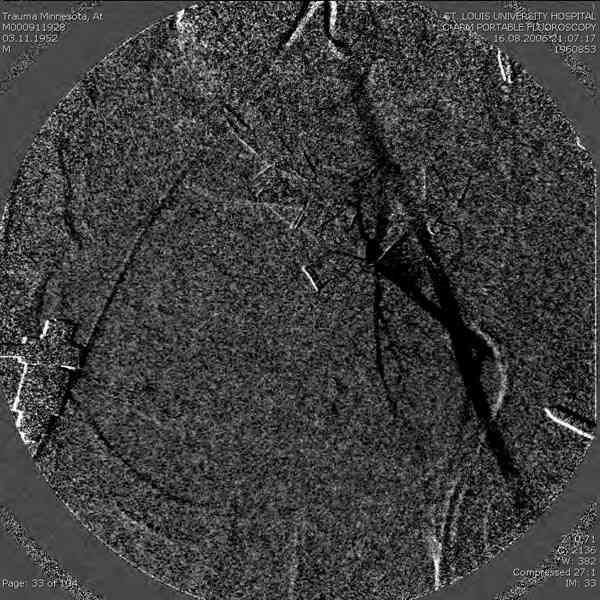

Примерно такой фиксатор наложил вчера ночью, но патология была экстренная травма: больному 53 года, поступил после мотоциклетной травмы, черепно-мозговой, абдоминальной, челюстно лицевой с потерей одного глаза, сосудистой и из скелета перелом крестца слева с диастазом симфиза и множественные переломы ребер.

Здесь соблюдался алгоритм больному с внутритазовым кроветечением после нестабильного перелома таза.

Для стабилизации перелома и кровопотери, сперва была попытка наложения простыни вокруг таза для уменшения объема таза. Для оперативного доступа в области живота и передней части таза простыню заменили на Beam Bag (матрац который после удалении воздуха принимает контуры тела).

Одновременно с хирургами, которые занялись ксплоративной лапаротомией, мы приступили к фиксации временным аппаратом для уменьшения диастаза симфиза. После установки аппарата удалось стабилизировать давление, потом наше место занял сосудистый хирург, который нашел кровоточащую левую артерию epigastrica. Кровоточаший сосуд затромбизировал эндоваскулярно введением 4 coil placement.

Много кровепотери было из лицевых ран. Кроме забрюшинной гематомы, крови накопилось в абдоминальной части между мышечными стенками и под кожей. Кровопотерю заместили более 20 доз препаратов крови и INR опустился изначалнего 9.5 до 1.0 в конце. Находится в реанимации, стабильный, надеемся через несколько дней займемся окончательной фиксацией переломов костей таза.